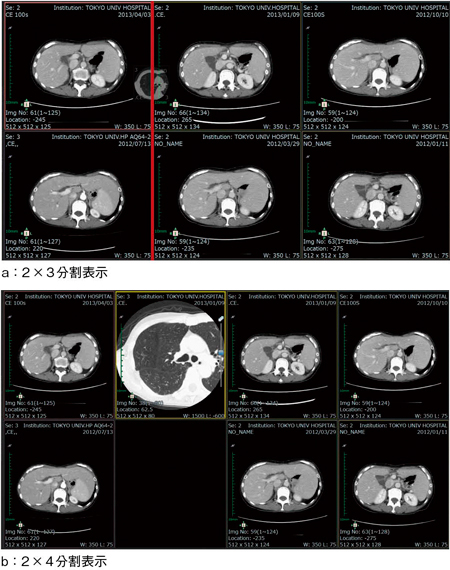

図3 ドラッグ&ドロップによるレイアウト変更

a:サムネイルを画像の境界線(─)上にドラッグ&ドロップする。

b:ドロップした位置に自動的に列が増え,狙い通りの位置に比較画像を配置できる。